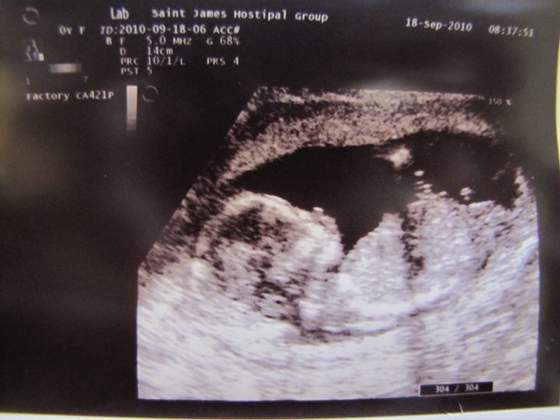

Dzień dobry, ja tak tylko na chwilę bo nie mam siły na nic :-( Wczoraj kolega nas wystawił z tym weselem i nie jedziemy na nie ostatecznie. A mało tego jeszcze miałam z koleżanką wypadek - hamulec nie zadziałał i wbiłyśmy się w inne auto - na szczęście straty niewielkie i nikomu nic się nie stało. Ale mandat na 100zł dostałam :-( A nie chciałam kumplowi robić problemów z badaniami technicznymi to przyjęłam ten durny mandat chociaż nie była moja wina :-( Tak więc jestem stówę w plecy a na dodatek nażarłam się tyle nerwów że masakra. Bo jak policja była bardzo sympatyczna (kobitka się zapytała czy karetki nie wezwać bo w ciąży to lepiej sprawdzić czy nic mi nie jest) tak szczyl z drogówki pożal się boże jaki dupek